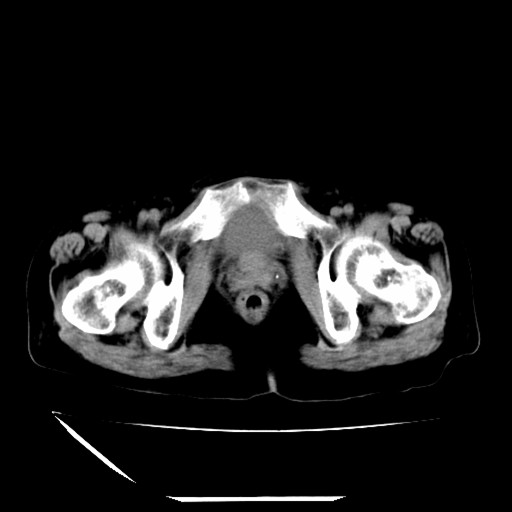

标题: CT16840:女-63岁,下腹部疼痛, [打印本页]

标题: CT16840:女-63岁,下腹部疼痛,

道格拉斯窝内少量积液。

盆腔少量积液   支持

支持 阑尾炎,盆腔少量积液。